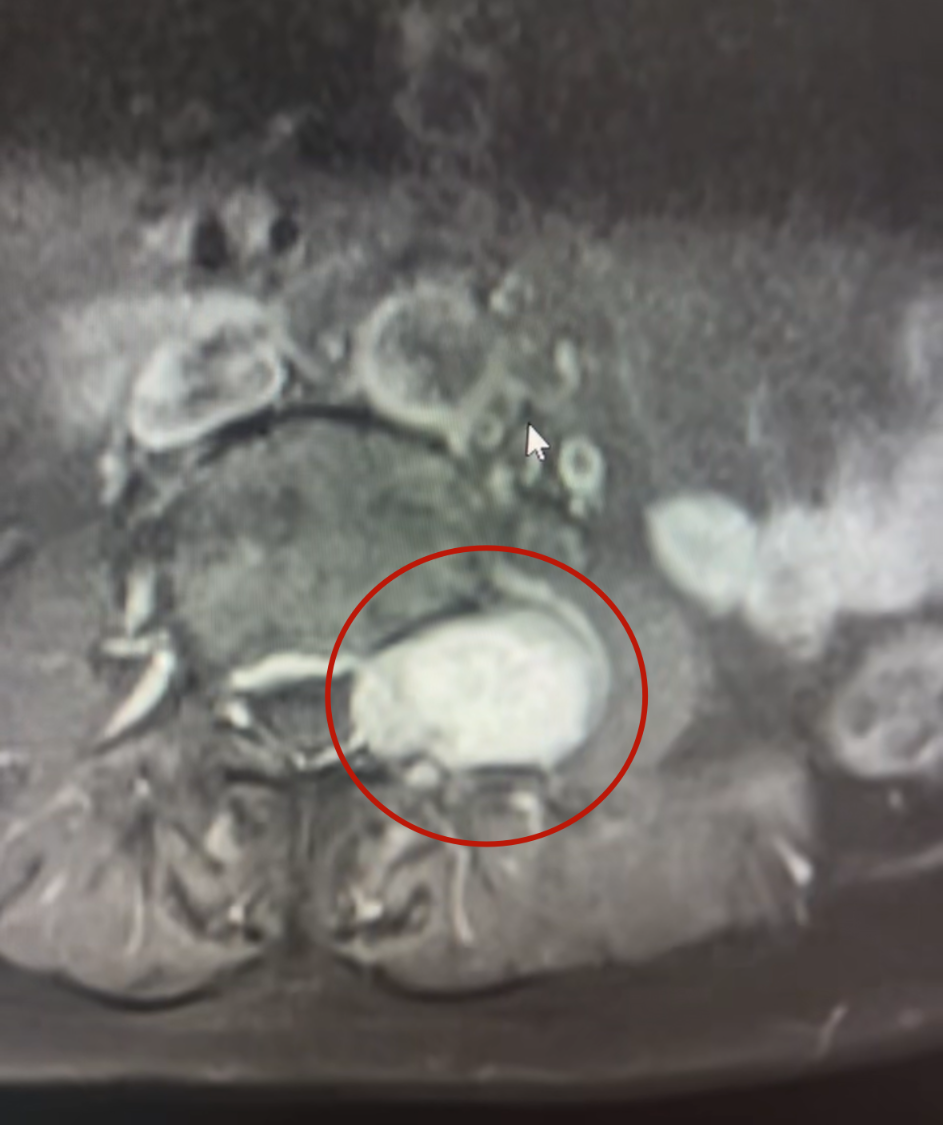

不久前,徐阿姨因心臟不適入住省榮軍醫(yī)院心內(nèi)科。在多學(xué)科會(huì)診中,醫(yī)生發(fā)現(xiàn)她腰椎存在異常,進(jìn)一步檢查顯示:她的腰椎椎管內(nèi)外,長(zhǎng)著一顆4cm×5cm大小的“啞鈴狀”腫瘤。

“腫瘤一半在椎管內(nèi),一半突出到椎間孔外,像啞鈴一樣卡在神經(jīng)通道上,已經(jīng)把椎骨都?jí)鹤冃瘟恕!睉?yīng)國(guó)政副主任醫(yī)師解釋道。這正是導(dǎo)致徐阿姨長(zhǎng)期左下肢麻木、無(wú)力,并出現(xiàn)嚴(yán)重漏尿,只能長(zhǎng)期使用尿不濕的根源。

▲腫瘤使錐體變形,腰大肌受壓

▲腫瘤浸入椎管,壓迫神經(jīng)